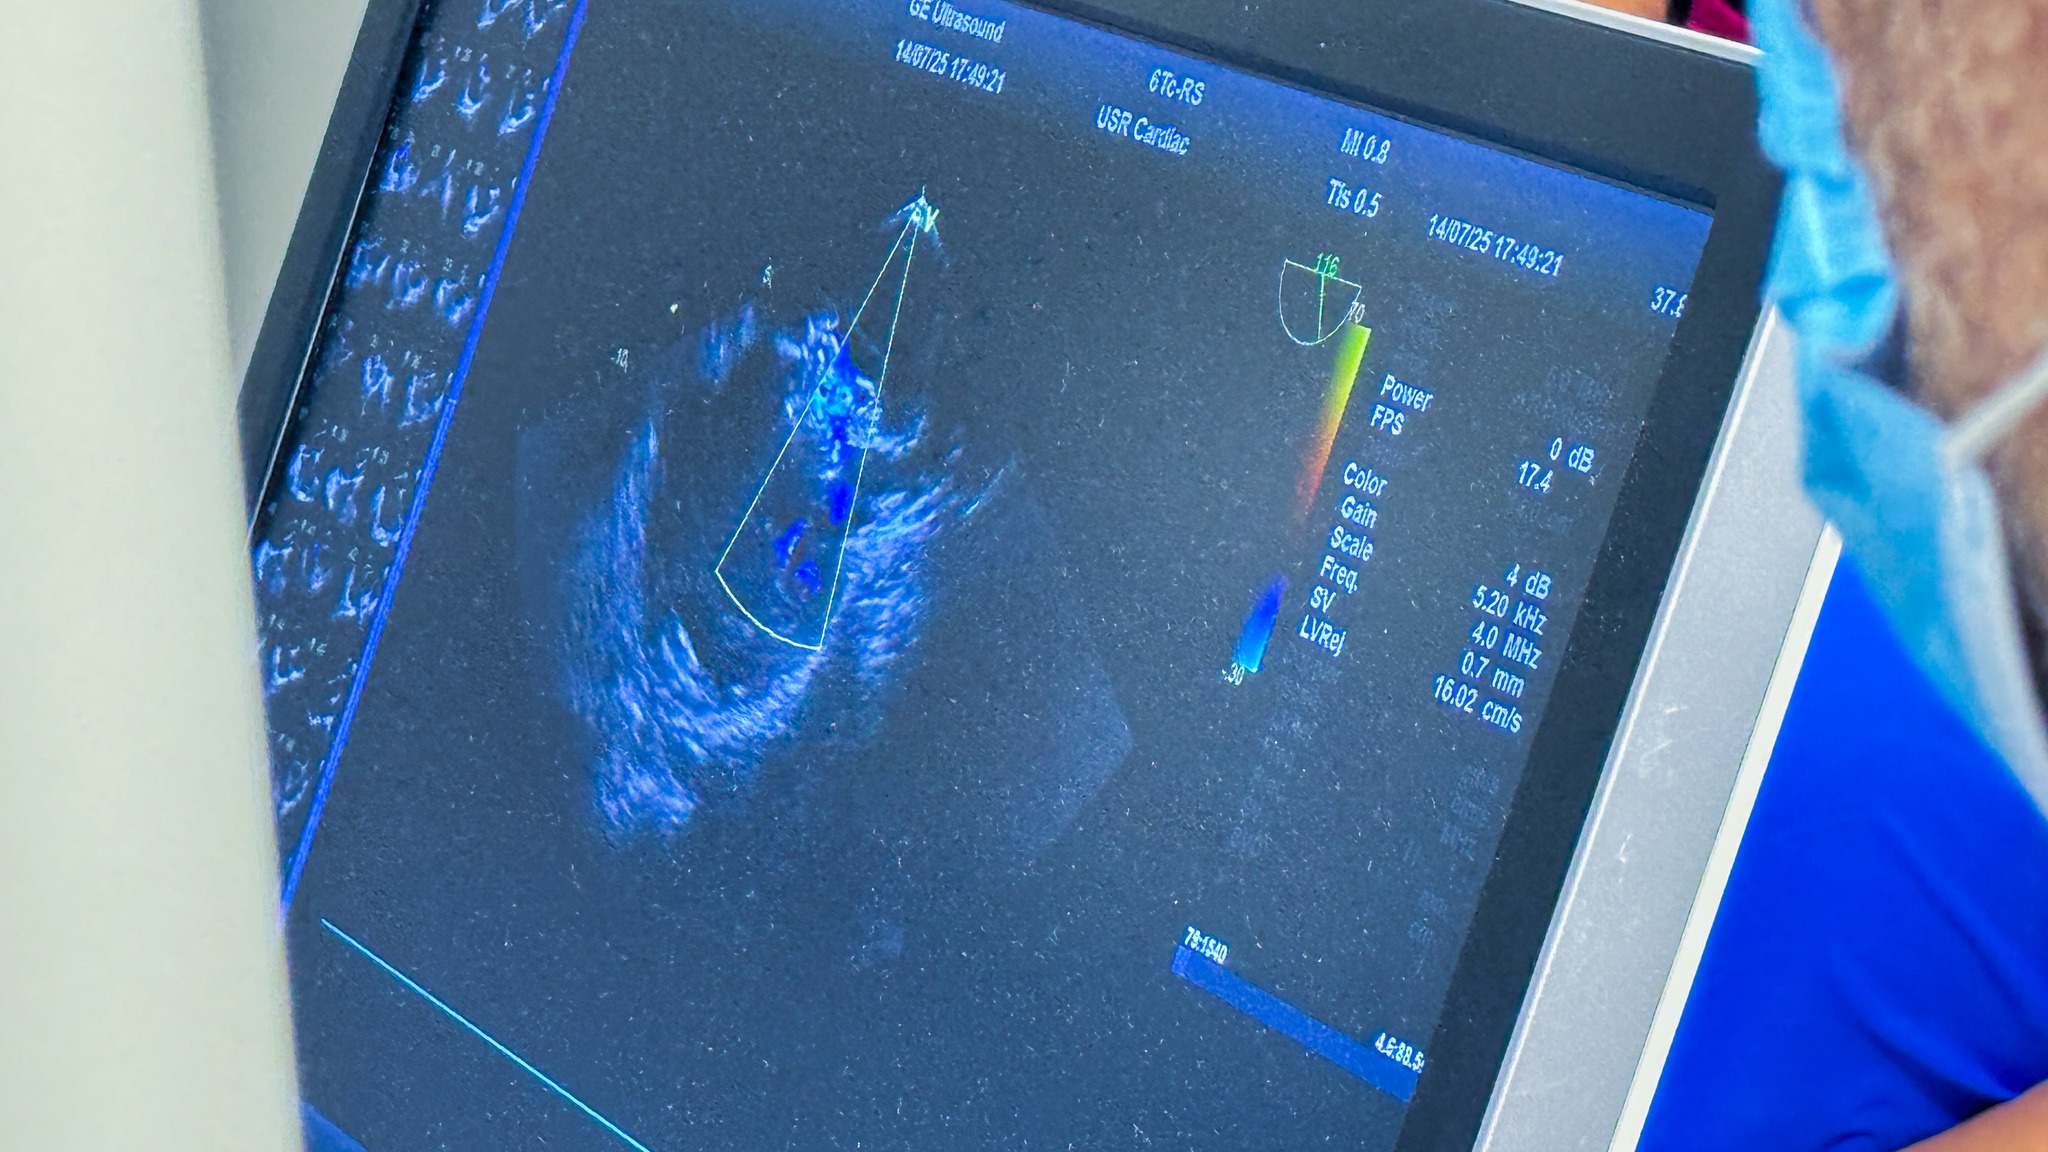

Historyczny zabieg w garwolińskim szpitalu. Po raz pierwszy zamknięto ASD bez operacji

Autor: SP ZOZ Garwolin